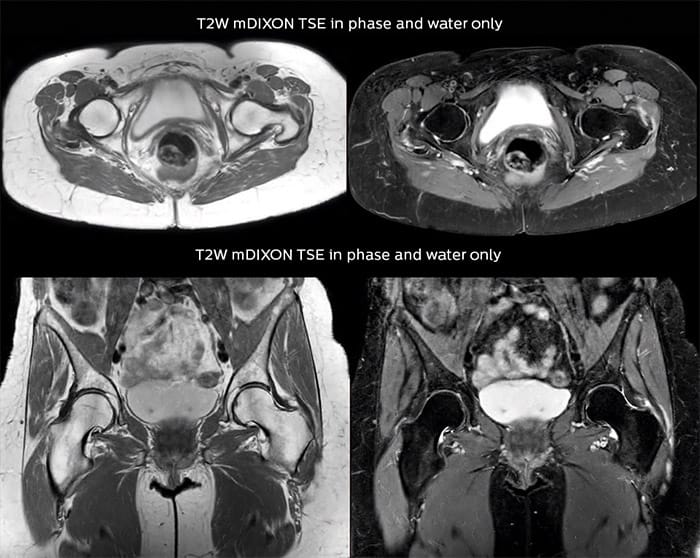

Add fat suppressed imaging without time penalty for peripheral joints

“In peripheral joints, mDIXON TSE imaging aids in diagnosing injuries in ligaments or tendons, for imaging degenerative and inflammatory pathologies such as osteoarthritis and rheumatologic disorders and for oncological exploration.”

“For tendon and ligament assessment around knee, ankle, hip and elbow, mDIXON TSE contributes to diagnostic confidence thanks to having images both with and without fat suppression – and without time penalty. This is possible because 2-point mDIXON is faster than the common 3-point Dixon method. It can also increase efficiency as it helps avoid having to add scans during the exam.”

Amazing quality of fat suppression

“In peripheral joints, we get good image quality in difficult areas with mDIXON TSE.

Fat suppressed images appear homogeneous over the entire image, even with large coverage at 3.0T – for instance in scapular or hip girdles – or in the bearing areas or around metal prostheses, where fat suppression is often deficient with STIR or spectral fat suppression, causing diagnostic difficulties. If a diagnostic image is right the first time, we don’t need to repeat or add a sequence.”

“mDIXON TSE sequences allow simultaneous characterization of morphological changes from the in-phase T2-weighted images and visualization of edematous changes, thanks to the water T2-weighted images from the same acquisition. Anatomical and morphological considerations could be a partial or complete ligament tear, a bony avulsion or hematoma.”

“For soft tissue assessment mDIXON brings similar benefits. For example in one T2-weighted mDIXON TSE acquisition, having the multiple contrasts helps us assess abnormalities in peripheral nerves fascicles, which may be due to anatomical or inflammatory changes..”

“Fat suppressed images appear homogeneous over the entire image, even at 3.0T.”